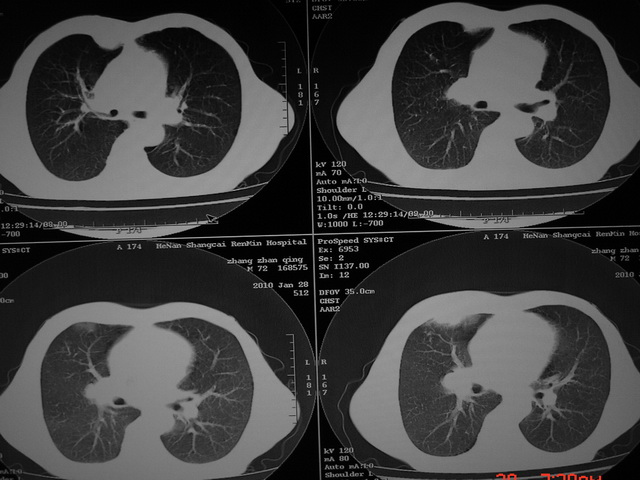

标题: CT24386:M 72岁农民 右侧胸痛6月余,咳嗽,无发热、咯血等 [打印本页]

xx m 72岁农民 右侧胸痛6月余,咳嗽,无发热、咯血等

右下周围型肺癌,并右肺门、纵膈淋巴结、内乳淋巴结转移,右胸膜转移累及前胸壁。鉴别:脓肿、tb、淋巴瘤。病理类型可能为大细胞型。

这个病人有点复杂了,上纵隔像是占位,右肺下叶见壁光整厚壁空洞加液平,像是肺脓肿,中叶病灶牵涉到胸膜及胸壁,形态看像是炎性病变,总之不能除外恶性病变,还是穿刺或增强后再说。

右下周围型肺癌。偏心空洞形成伴感染。

右下周围型肺癌伴转移

支持2搂,考虑右肺下叶周围性肺癌伴肺门及纵膈淋巴结转移!右侧前纵膈病灶,还是一元论考虑为胸壁或胸膜转移瘤。

右侧周围性肺癌,胸膜转移。

支持 右肺下叶周围型肺癌并右肺门、纵膈淋巴结、内乳淋巴结转移,右胸膜转移累及前胸壁。